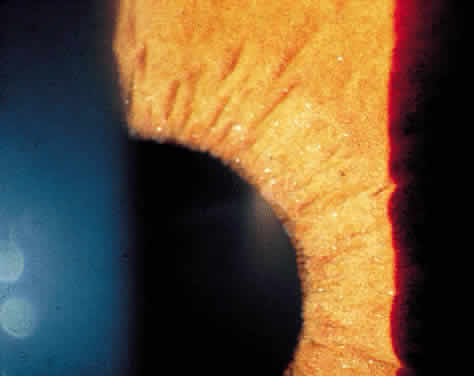

KERATIC PRECIPITATES

Clusters of inflammatory cells deposited on the endothelial surface of the cornea are known as keratic precipitates. The cells, which have been deposited from the aqueous humor, are often found inferiorly on the cornea in a linear vertical formation (Turk's line) or in the form of a base-down triangle (Arlt's triangle; Fig. 2). The inferior corneal distribution results from convection currents in the anterior chamber that rise along the warm iris and fall along the cool cornea. Exceptions to the rule of inferior distribution of keratic precipitates include inflammation secondary to herpes simplex and zoster, cytomegalovirus, and Fuchs' heterochromic iridocyclitis, which result in fine stellate keratic precipitates, often throughout the whole cornea. Sarcoidosis and VKH may also result in keratic precipitates distributed above the midline but these keratic precipitates tend to be larger and greasier in appearance than those associated with Fuchs' or herpetic iridocyclitis.

The cells that precipitate on the corneal endothelium reflect the composition of those in the aqueous humor. In acute inflammation, polymorphonuclear leukocytes predominate, whereas in chronic inflammation lymphocytes, plasma cells and pigment are more common.8 Fine fibrin dusting may also be present, alone or among the keratic precipitates. Fibrin is a prominent feature of the keratic precipitates of Fuchs' iridocyclitis, forming the bridges and stellate arms of the keratic precipitates.

In addition to size, shape, and distribution of keratic precipitates, color may be an important characteristic. Fresh keratic precipitates tend to be white and round, whereas older keratic precipitates may be pigmented, faded, or have an irregular crenelated appearance. Descemet's membrane may cover old keratic precipitates, imparting a glassy or ghost-like appearance (Fig. 3). Large greasy-white keratic precipitates approaching 1 mm in diameter are often termed mutton-fat keratic precipitates and represent clusters of macrophages and epithelioid cells (Fig. 4). These are pathognomonic of granulomatous inflammation.

Iris nodules may be gray or white and translucent and are often covered with pigment. Masses at the pupillary border are called Koeppe nodules, whereas those on the anterior surface of the iris are called Busacca nodules (Fig. 7; see Fig 2). Busacca nodules are evidence of granulomatous inflammation, and Koeppe nodules are often located in areas that subsequently develop posterior synechiae. The presence and location of nodules should be carefully diagrammed, and every effort must be made to keep the pupil moving, thereby preventing the development of permanent iridolenticular adhesions.